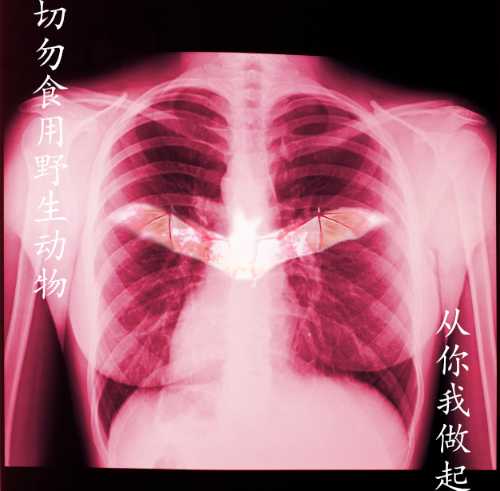

2019级《ID版式设计》优秀作业